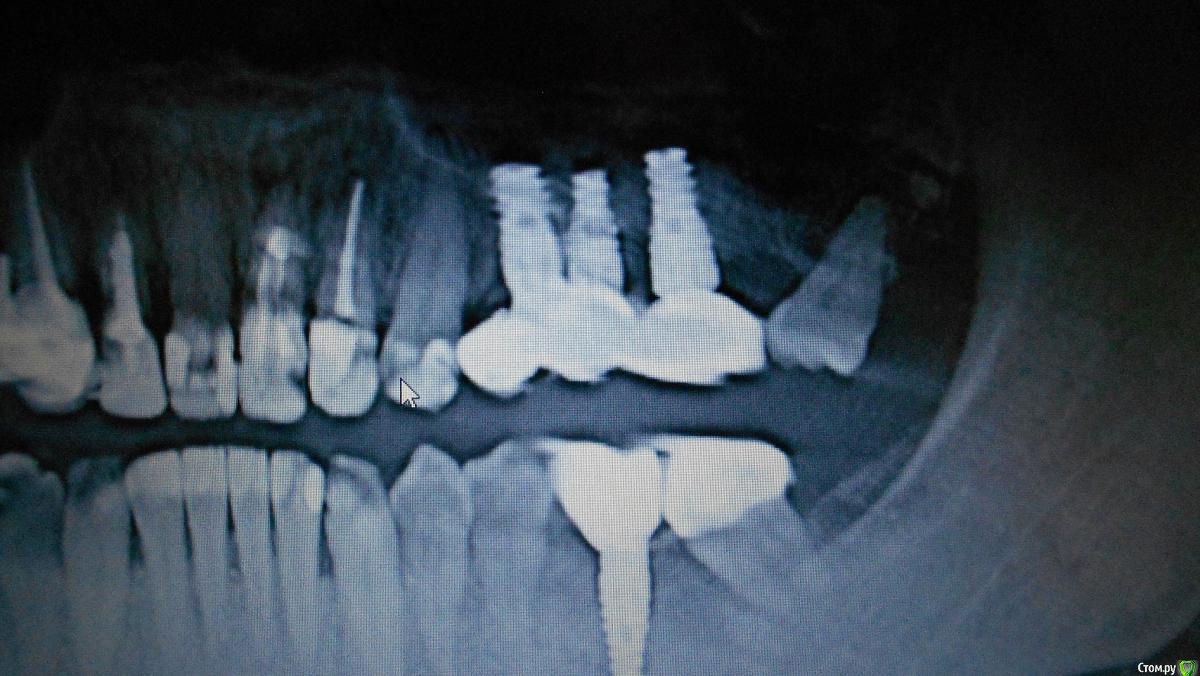

Oks72 Опубликовано 22 февраля, 2018 Автор Поделиться Опубликовано 22 февраля, 2018 (изменено) Добавила снимки. Изменено 22 февраля, 2018 пользователем Oks72 Ссылка на комментарий

Bier Опубликовано 22 февраля, 2018 Поделиться Опубликовано 22 февраля, 2018 если эстетически работа вас не устраивает, то необходимо удалить ближний имплантат, потом поставить в более выгодную позицию. Ссылка на комментарий